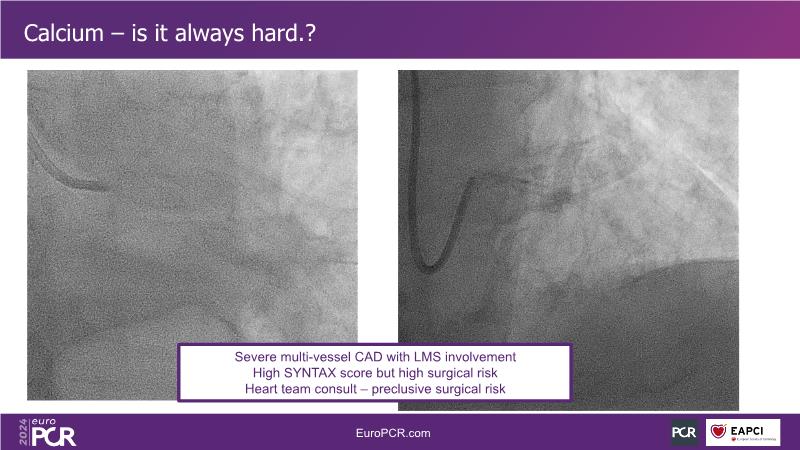

Delve into this EuroPCR 2024 session to gain insights into NIRS IVUS, exploring its applications, supported by current data, and understanding its clinical significance. Learn how to utilize NIRS IVUS in PCI planning through case examples, addressing lesion characteristics such as length and calcific nodules. Explore local and systemic strategies for modifying plaque vulnerability and envision the future role of NIRS IVUS in PCI, with a glimpse into upcoming studies on the subject.